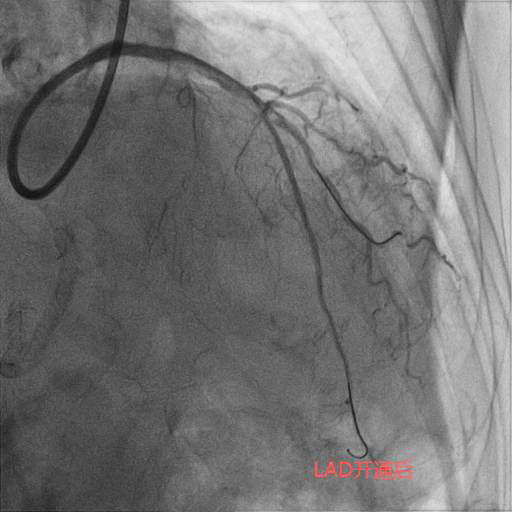

今年83岁高龄的刘老先生,退休前从事地质工作,平素身体硬朗,但近期发现快走后出现憋气症状,到某医院就诊,冠状动脉造影检查为三支病变,前降支(LAD)、回旋支(LCX)、右冠状动脉(RCA)均为完全闭塞病变且伴重度钙化。在经过近一个小时的尝试后,闭塞血管未开通,建议药物治疗。但药物治疗并未缓解刘老先生的症状,心功能反而一步步下降。后来患者及家属抱着极大的期望去某著名心脏专科医院就诊,经过半个小时的尝试后开通失败,并告知患者家属这样的血管不可能开通,冠状动脉搭桥术是唯一的出路。但是搭桥手术对于一位83岁高龄的老人来说无疑是一个艰难巨大的挑战。两次失败手术的打击使得刘老先生的身体状态每况愈下,稍事活动就气喘吁吁,逐渐对生活失去了信心。后来家属辗转打听到北京潞河医院心内科翟光耀主任团队致力于冠状动脉复杂手术,抱着最后一搏的想法,在经过两个月的药物调整后能耐受再次手术的前提下,刘老先生再次躺在了手术台上。术中,冠状动脉造影结果让翟光耀主任团队意识到了这次手术的难度之大,风险之高。三支主干闭塞,之前手术开通失败已造成血管近端夹层,闭塞的血管(尤其是RCA)全程重度钙化,近乎全程闭塞,开通血管无疑在花岗岩上开凿隧道。在经过近4个小时的不懈努力,团队终于成功开通了难度最大的RCA并植入支架,观察一天后顺利出院。 一个月后,刘老先生闭塞的LAD也成功开通。现在,刘老先生身体恢复良好,如获新生!